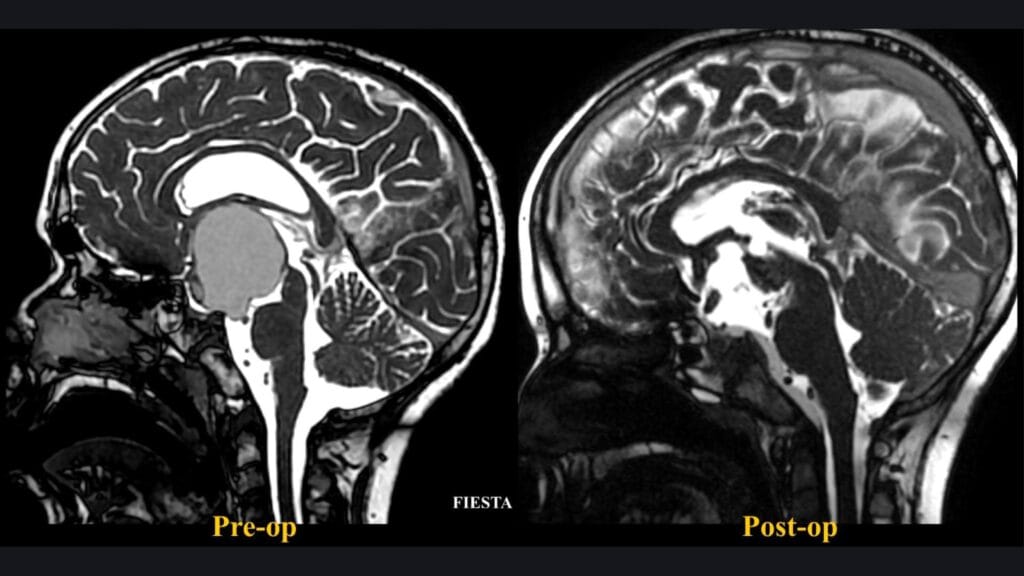

Resección microquirúrgica de un meningioma petroclival gigante

El Dr. Luis Borba realiza la resección completa de un meningioma petroclival gigante mediante abordaje petroso posterior.